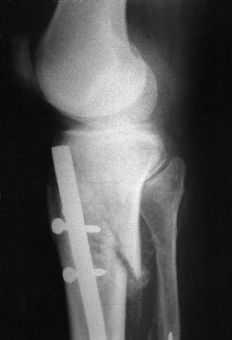

El tiempo medio operatorio fue de 63 minutos (mínimo: 45 y máximo: 90 minutos). Se utilizó un clavo de 8 mm en 29 casos y de 9 mm en 32; se produjo una fractura intraoperatoria de la cortical posterior (Fig. 1). La dinamización se llevó a cabo en una media de 9 semanas (mínimo: 5 y máximo: 20 semanas). La carga completa postoperatoria se inició a una media de 8 semanas (mínimo: 1 y máximo: 19 semanas) tras la intervención. Catorce (6,2%) de los 226 tornillos empleados se doblaron o rompieron (tres tornillos estáticos proximales, uno dinámico proximal y 10 tornillos distales). En tres pacientes el clavo no fue dinamizado antes de cargar peso. En uno de ellos se rompieron todos los tornillos y en dos se rompió el estático proximal y los dos distales (Fig. 2). En tres pacientes se rompieron los tornillos distales a pesar de que el clavo había sido dinamizado.

Angle y Blue1 encontraron que las fracturas tratadas con enclavados sin fresado consolidaron en 34 semanas, mientras que las tratadas con enclavados fresados tardaron 22 semanas. Court-Brown y cols.,3 comparando fracturas diafisarias cerradas de la tibia tratadas mediante enclavado con y sin fresar, llegando a la conclusión que el tiempo de consolidación para los pacientes tratados mediante enclavado fresado fue de 15 semanas, significativamente menor que para los enclavados sin fresar que fue de 22 semanas. Todos los pacientes tratados con clavos fresados consolidaron sin problemas, mientras que el 20% del grupo de pacientes tratados sin fresar requirió un cambio del clavo por otro fresado para lograr la consolidación. Gregory y Sanders5 encontraron que el tiempo medio de consolidación fue de 16 semanas en un grupo de 38 fracturas diafisarias cerradas de tibia tratadas mediante clavos no fresados. Nuestra serie tiene una alta tasa de consolidación (98%). Howard y cols.,9 en una serie de 40 fracturas cerradas de tibia obtienen una tasa de consolidación del 97,5% con el clavo de Lottes. Gregory y San-ders5 en su serie de 38 fracturas diafisarias de tibia tratadas mediante el clavo intramedular sin fresado AO/ASIF han tenido un 8% de pseudoartrosis. Duwelius y cols.4trataron 31 fracturas cerradas de la tibia con este mismo clavo y 30 de ellas (97%) consolidaron en 1 año. Anglen y Blue1 constataron un 21% de pseudoartrosis en 23 enclavados sin fresar de tibia, no habiendo clavos rotos en esta serie. Whittle y cols.24 en una serie de 130 fracturas tibiales estabilizadas con clavos sin fresar encontraron un 3% de clavos rotos. Todos los casos de rotura de clavo ocurrieron en fracturas abiertas con retardo de consolidación, y todos los clavos estaban estáticamente bloqueados durante la rotura del clavo. De los 226 tornillos de bloqueo usados en nuestra serie 14 se doblaron o rompieron, en algunos probablemente porque el clavo no fue dinamizado antes de cargar peso. En tres pacientes los tornillos distales se rompieron aunque el clavo había sido dinamizado. Gregory y Sanders5 tuvieron 12 (15%) tornillos rotos de los 80 usados. Estos autores permitían la carga sin dinamizar del clavo, y esto podría influir en que los tornillos estáticos de bloqueo se rompieran.